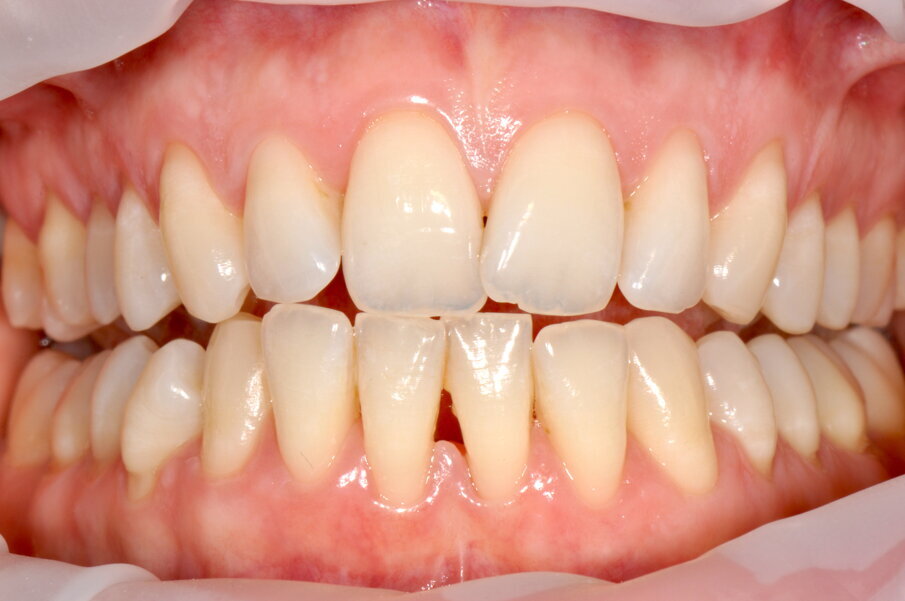

Paziente di sesso femminile di anni 27 con anamnesi generale negativa e senza storia di malattia parodontale, si presenta in prima visita lamentando sanguinamento gengivale durante le normali procedure di igiene orale domiciliare.

Viene quindi raccolta la documentazione fotografica ed effettuato lo screening PSR (Periodontal Screening and Recording), con risultato associabile a gengivite generalizzata (valore 1 e 2 per tutti i sestanti sia superiori che inferiori), con presenza di abbondanti depositi di placca e tartaro.

All’esame orale si evidenziano depositi di tartaro, in particolare nel quinto sestante nella zona linguale, e depositi di placca generalizzati (IP=2). I sondaggi parodontali risultano essere fisiologici con presenza di sanguinamento marginale e al sondaggio.